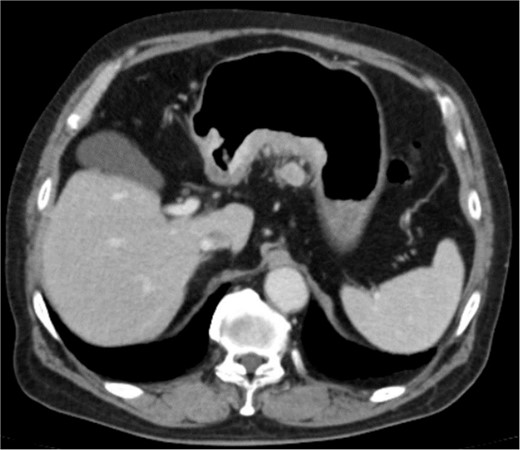

An 83-year-old man visited due to discomfort in the stomach. The patient underwent upper endoscopy that revealed a large tumor in the stomach (Fig. 1). The histological diagnosis was moderately differentiated tubular adenocarcinoma. Computed tomography (CT) revealed thickening of the gastric wall and bulky lymph nodes around the pancreas (Fig. 2). The patient underwent subtotal gastrectomy with Roux-en-Y reconstruction. The metastatic lymph nodes around the pancreas were removed. Abdominal drainage from Winslow’s foramen was performed. The pathological result was pT4aN3aM0 and Stage IIIB [1].

Clinical findings of contrast-enhanced CT. CT revealed the thickness of gastric wall and enlarged lymph nodes of lesser curvature side.

Diagnosis of postoperative duodenal perforation. CT showed ascites in subdiaphragmatic space (arrow) and around duodenal stump (circle) at POD 8.